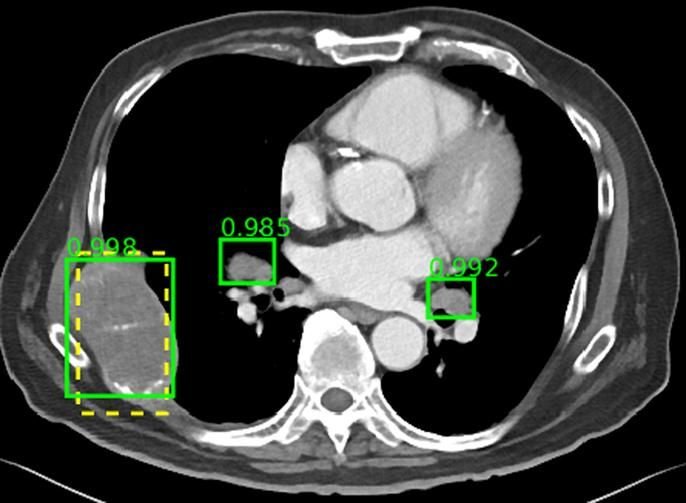

Percepción de la inteligencia artificial en la comunidad radiológica argentina

05 noviembre 2024

Aunque el grado de conocimiento acerca de la IA en la comunidad radiológica argentina es moderado, encontramos un alto interés y expectativas, y un bajo nivel de miedo o rechazo. Las sociedades radiológicas argentinas deberían desarrollar cursos de formación en IA. Rev Argent Radiol. 2024